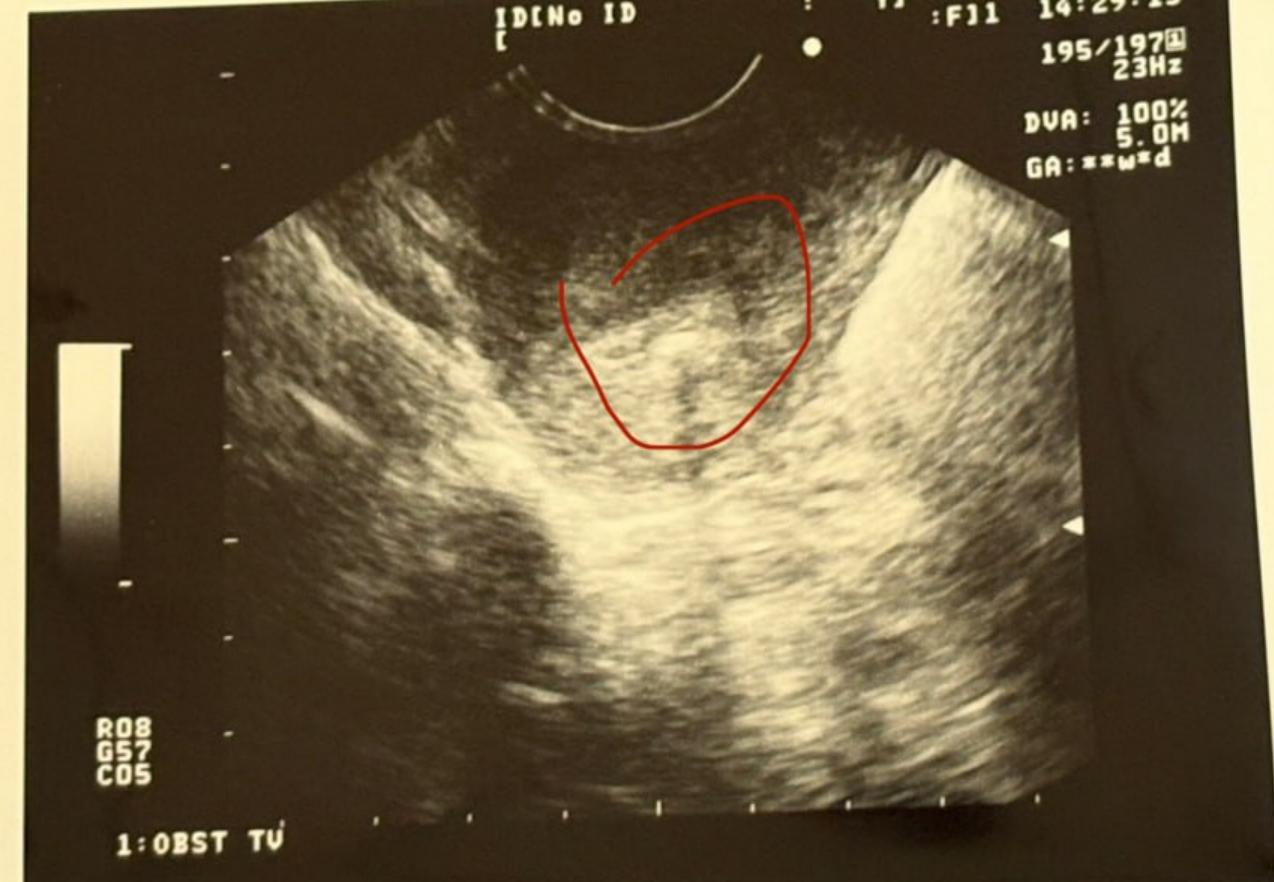

1月24日,孕7周,已成功看到胎心。

小小的心跳如期而至,生命的第一份回應悄然出現。